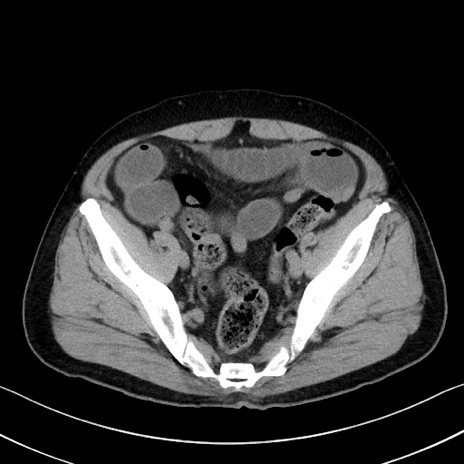

症例35(横断像)

【症例】70歳代 男性

【主訴】腹部膨満、嘔吐

【現病歴】昨日より腹部膨満感出現。本日増悪し、仙痛出現。嘔吐あり、受診。

【既往歴】糖尿病、胆摘後

【身体所見】BP 149/80mmHg、HR 74/min、BT 35.9℃、腹部:膨満、軟、圧痛なし。腸雑音減弱あり。上腹部正中切開瘢痕あり。

【データ】WBC 13500、CRP 1.72